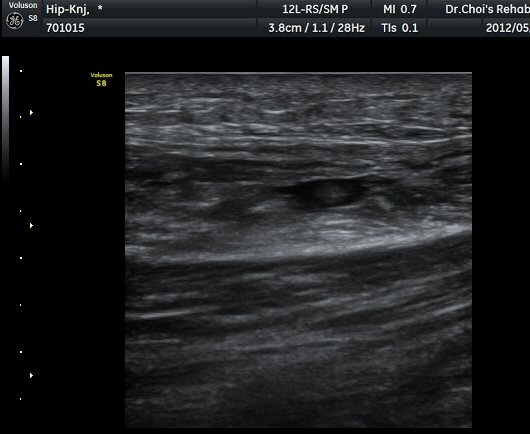

´ëÅðÁ÷±Ù Á¾´Ü¸é°Ë»ç¿¡¼­ ±ÙÀ°³»¿¡ ¼±»óÀÇ Àú¿¡ÄÚ °¢±ØÀÌ °üÂûµÈ´Ù(±×¸² 4, 5).